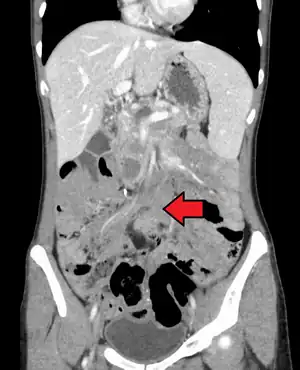

| Desmoid tumor as seen on CT scan | |

Aggressive fibromatosis or desmoid tumor is a rare condition. Desmoid tumors arise from cells called fibroblasts, which are found throughout the body and provide structural support, protection to the vital organs, and play a critical role in wound healing. These tumors tend to occur in women in their thirties, but can occur in anyone at any age. They can be either relatively slow-growing or malignant. However, aggressive fibromatosis is locally aggressive and can cause life-threatening problems or even death when they compress vital organs such as intestines, kidneys, lungs, blood vessels, or nerves. Most cases are sporadic, but some are associated with familial adenomatous polyposis (FAP). Approximately 10% of individuals with Gardner's syndrome, a type of FAP with extracolonic features, have desmoid tumors.[1]